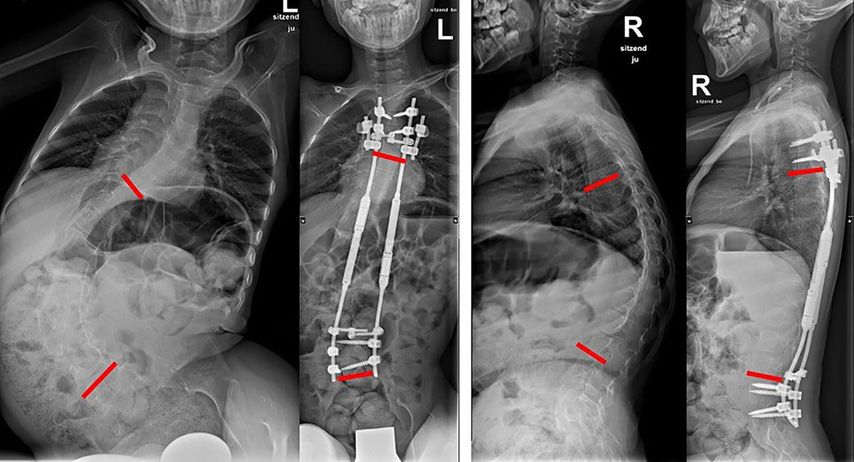

Die Distraktion über die Stäbe kann mit sogenannten „traditional growing rods“ erfolgen, bei denen zumindest einmal jährlich eine Operation zum Nachspannen erfolgen muss. Hier sind daher – wenn auch nur kurze – wiederholte Narkosen und stationäre Spitalsaufenthalte notwendig. Die Entwicklung magnetisch distrahierbarer Stäbe, welche im ambulanten Setting mittels eines externen Magnetmotors nachgestellt werden, erübrigt das operative Nachspannen (Abb.2).

Abb. 2: Prä- und postoperative Röntgenbilder eines 10-jährigen Burschen mit spinaler Muskelatrophie. Es erfolgte die Implantation magnetisch distrahierbarer Stäbe mit Verankerung über Pedikelschrauben und Rippenhaken. Sowohl Skoliose und Beckenschiefstand als auch Kyphose konnten reduziert werden